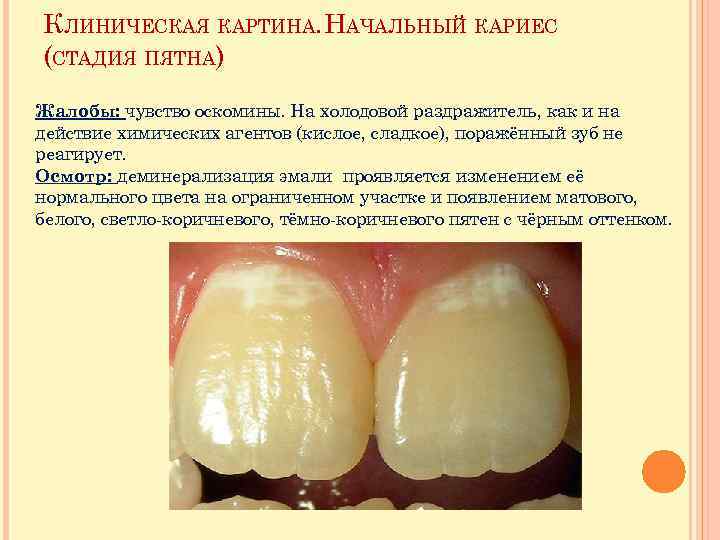

КЛИНИЧЕСКАЯ КАРТИНА. НАЧАЛЬНЫЙ КАРИЕС (СТАДИЯ ПЯТНА) Жалобы: чувство оскомины. На холодовой раздражитель, как и на действие химических агентов (кислое, сладкое), поражённый зуб не реагирует. Осмотр: деминерализация эмали проявляется изменением её нормального цвета на ограниченном участке и появлением матового, белого, светло-коричневого, тёмно-коричневого пятен с чёрным оттенком.

КЛИНИЧЕСКАЯ КАРТИНА. НАЧАЛЬНЫЙ КАРИЕС (СТАДИЯ ПЯТНА) Жалобы: чувство оскомины. На холодовой раздражитель, как и на действие химических агентов (кислое, сладкое), поражённый зуб не реагирует. Осмотр: деминерализация эмали проявляется изменением её нормального цвета на ограниченном участке и появлением матового, белого, светло-коричневого, тёмно-коричневого пятен с чёрным оттенком.

КЛИНИЧЕСКАЯ КАРТИНА. НАЧАЛЬНЫЙ КАРИЕС (СТАДИЯ ПЯТНА) Процесс начинается с потери блеска эмали на ограниченном участке. Обычно это происходит у шейки зуба рядом с десной. Поверхность пятна гладкая, острие зонда по ней скользит. Пятно окрашивается раствором метиленового синего. Пульпа зуба реагирует на ток силой 2 -6 мк. А. При трансиллюминации оно выявляется независимо от локализации, размеров и пигментированности. Под влиянием ультрафиолетовых лучей в области кариозного пятна наблюдается гашение люминесценции, свойственное твёрдым тканям зуба.

КЛИНИЧЕСКАЯ КАРТИНА. НАЧАЛЬНЫЙ КАРИЕС (СТАДИЯ ПЯТНА) Процесс начинается с потери блеска эмали на ограниченном участке. Обычно это происходит у шейки зуба рядом с десной. Поверхность пятна гладкая, острие зонда по ней скользит. Пятно окрашивается раствором метиленового синего. Пульпа зуба реагирует на ток силой 2 -6 мк. А. При трансиллюминации оно выявляется независимо от локализации, размеров и пигментированности. Под влиянием ультрафиолетовых лучей в области кариозного пятна наблюдается гашение люминесценции, свойственное твёрдым тканям зуба.